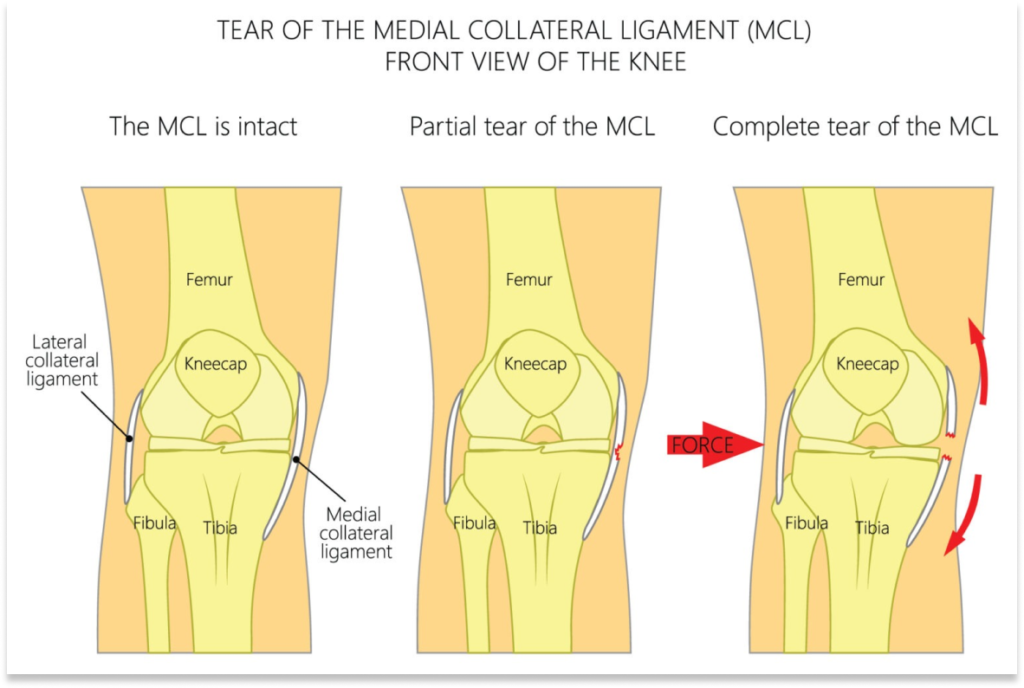

The Medial Collateral Ligament (MCL) and the Lateral Collateral Ligament (PCL) are ligaments in the knee that work jointly to provide support and stability to the knee. The MCL and LCL ligaments are two of the four major ligaments in your knee. The other two ligaments are the ACL and PCL Ligaments (Anterior Cruciate Ligament & Posterior Cruciate Ligaments).

The MCL is located along the inside of the knee and connects the femur to the tibia. The MCL is responsible for keeping the knee from bending out.

The LCL runs along the outside of the knee and connects the femur to the fibula.

The LCL stops the knee from bending in.

- The MCL is the ligament located on the inside of your knee joint. It links your thighbone (femur) and shinbone (tibia).

- The LCL is the ligament located on the outside of your knee linking the thighbone and calf bone (fibula).